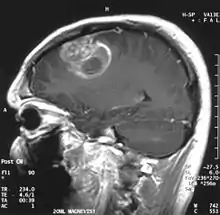

La tomodensitométrie (TDM) et L'imagerie par résonance magnétique (IRM) peuvent détecter efficacement une néoplasie dans le cerveau. L'IRM est plus sensible que la TDM pour identifier les lésions, mais présente des contre- indications pour les patients porteurs de stimulateurs cardiaques, de prothèses incompatibles, de clips métalliques et contre-indications. La TDM reste la méthode de choix pour détecter les calcifications au sein des lésions ou les érosions osseuses de la calotte ou de base du crâne. L'utilisation d' agents de contraste, iodés dans le cas du scanner et paramagnétiques (gadolinium) dans le cas de l'IRM, permet l'acquisition d'informations sur la vascularisation et l'intégrité de la barrière hémato-encéphalique, une meilleure définition de la tumeur tumorale par rapport à l' œdème environnant et à la génération d' hypothèses sur le degré de malignité. L'examen radiologique permet également d'évaluer les effets mécaniques et les modifications importantes des structures cérébrales résultant de la tumeur, telles que l' hydrocéphalie et les hernies, dont les effets peuvent être fatals. Enfin, en préparation à la chirurgie, ce diagnostic peut être utilisé pour déterminer la localisation de la lésion ou l'infiltration de la tumeur dans des zones vitales du cerveau. À cette fin, l'IRM est plus efficace que la tomodensitométrie car elle peut fournir des images en trois dimensions.

Sur-L'IRM montre une tumeur intracrânienne comme une lésion massive qui peut devenir plus luminescente après utilisation du produit de contraste. Cependant, il y a toujours une anomalie de signal dans -L'imagerie par résonance magnétique, qui indique la présence d'une néoplasie ou d'un œdème vasogénique. Habituellement, une luminescence accrue (amélioration du contraste) indique une tumeur d'un grade supérieur de malignité. Un anneau de contraste est caractéristique du glioblastome, avec la partie luminescente correspondant à la partie vitale de la tumeur maligne, et la plus foncée - zone hypointense correspondant à une nécrose tissulaire.

Glioblastome

Les tumeurs des cellules gliales les plus courantes et les plus malignes sont les glioblastomes. Ils consistent en une masse hétérogène de cellules d'astrocytome peu différenciées principalement chez l'adulte. Ils surviennent généralement dans les hémisphères cérébraux, plus rarement dans le tronc cérébral ou la moelle épinière. Sauf dans de très rares cas, comme toutes les tumeurs cérébrales, elles ne s'étendent pas au-delà des structures du système nerveux central.

Le glioblastome peut provenir d'une forme diffuse (II. grade) ou un astrocytome anaplasique (III. grade) développer. Dans ce dernier cas, il est dit secondaire. Cependant, lorsqu'elle survient sans antécédent ni signe de malignité antérieure, on parle de maladie primaire. Les glioblastomes sont traités par chirurgie, radiothérapie et chimiothérapie. Ils sont difficiles à guérir et rares sont les cas qui survivent au-delà de trois ans.